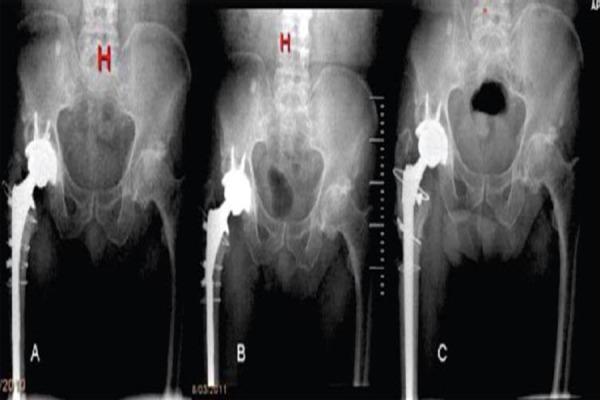

Mechanical failure of femoral stems of revision hip arthroplasty has been rarely reported. In the current study, the cause of two stem fractures, which occurred in vivo, was analysed with use of clinical and radiological data, and the functional result after revision is presented.

Two patients, A 70-year-old male and a 73-year-old female, both of Mediterranean ethnic, and both patients underwent a revision total hip replacement to an uncemmented extensively porous coated stem. Both stems suffered an implant fatigue in vivo at three years and at two years follow-up respectively.

Revision total hip arthroplasty is a procedure that will be performed more often the following years due to aging of population. Any orthopaedic surgeon performing hip surgery should be aware of the risk factors that can lead to total hip arthroplasty failure. In the analysed cases we can learn that the main factors related to this failure included the use of a small size stem (inferior to 14mm), an inadequate proximal osseous support because of trochanteric osteotomy, and a reduced preoperative bone stock. Although the use of cables has not been stated as a predisposing factor, we consider that they could also play a role in the development of this rare complication.